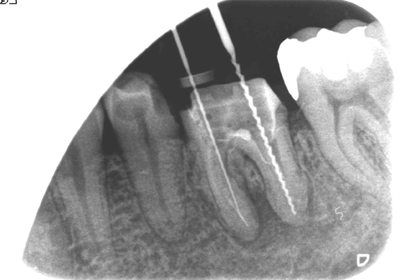

2Dのレントゲンではわずかな病巣としか見えませんが、3DのCTでは内部にかなり大きな病変が在るのが良くわかります。

治療前

治療後